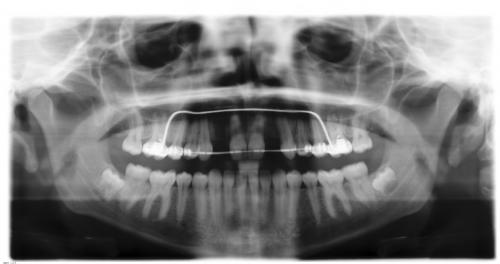

Nach Einsetzen der Implantate

Vor und nach der Implantation

Mundfotos im Vergleich